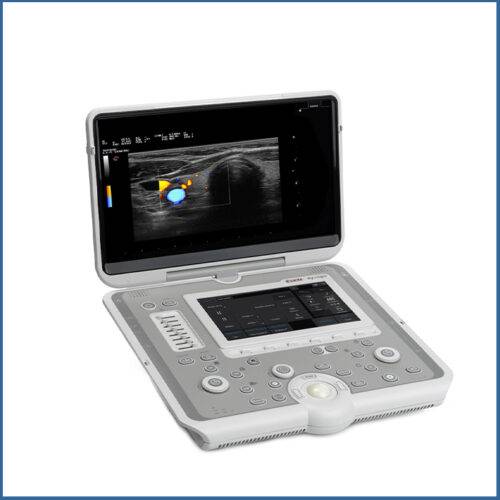

Φορητός έγχρωμος υπερηχογράφος, το πιο σύγχρονο στην κατηγορία του,

με Doppler, που φτάνει πέρα από τις προσδοκίες σας λόγω της συμπαγής

και μοντέρνας εμφάνισης του. Εξυπηρετεί τις ανάγκες όλων σχεδόν των ειδικοτήτων

και η λειτουργιά του χρώματος θα σας βοηθήσει στην αποτελεσματικότερη διάγνωση των λαβών.

Υπέρηχος Sonoscape E2

• 15,6¨ οθόνη HD LCD υψηλής ανάλυσης (με αυτόματη προσαρμογή φωτισμού)